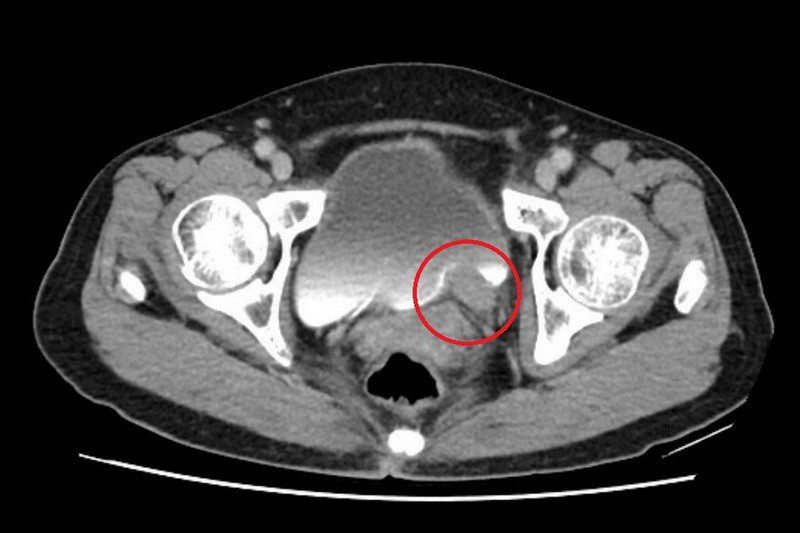

電腦斷層顯示,左側輸尿管末端有一約5公分大腫瘤。

67 歲的林女士一向健康,卻在近期出現間歇性的無痛血尿,她原本以為只是小問題,至台北慈濟醫院檢查後,竟發現左側輸尿管末端長了一顆5公分的腫瘤,並造成腎水腫情形。確診為輸尿管泌尿上皮癌後,許竣凱醫師先安排化療縮小腫瘤,再利用達文西手術切除腫瘤並重建輸尿管,成功保留腎臟功能,林女士術後追蹤至今,病情控制良好。